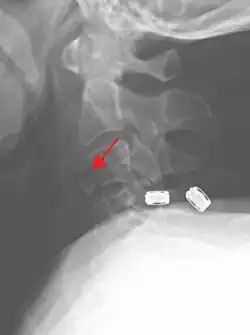

Radiographic detection

On CT scan or X-ray, a cervical fracture may be directly visualized. In addition, indirect signs of injury by the vertebral column are incongruities of the vertebral lines,[7] and/or increased thickness of the prevertebral space:[8]